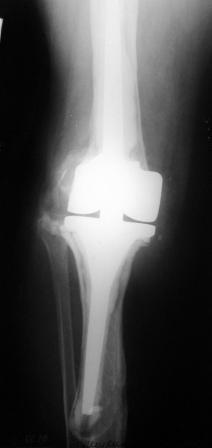

Хотелось бы услышать Ваше мнение о возможности и способе помощи

больной. 1939 г.р. В 1995г. эндопротезирование правого коленного

сустава протезом Феникс, в 1999г. в г. Томске - ревизия - ротационный

хинч W.Link. C 2005г. прогрессирует варусная деформация за счет

нестабильности тибиального компонента. Попытка ортезирования - без